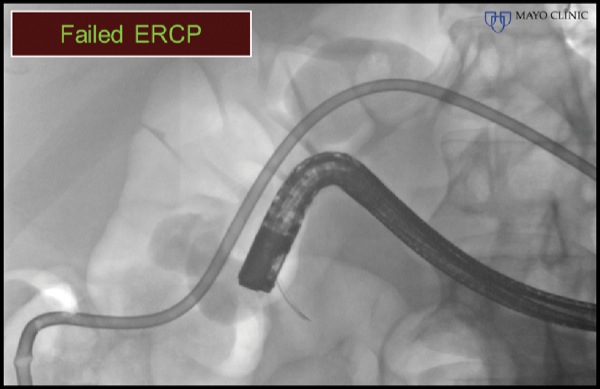

A 47-year-old man with a history of rectal adenocarcinoma and surgical resection with repeat colo-colonic anastomosis, radiation therapy, and chemotherapy presented with nausea, vomiting, dehydration, and obstructive jaundice. Abdominal CT demonstrated a large pancreatic head mass and duodenal obstruction (Figure 4A). ERP was attempted but failed because of duodenal tumor ingrowth, an inability to visualize the papilla, and duodenal obstruction (Figure 4B). The patient was referred for EUS-guided palliation of his obstructive jaundice.

Figure 4A.

Figure 4B.